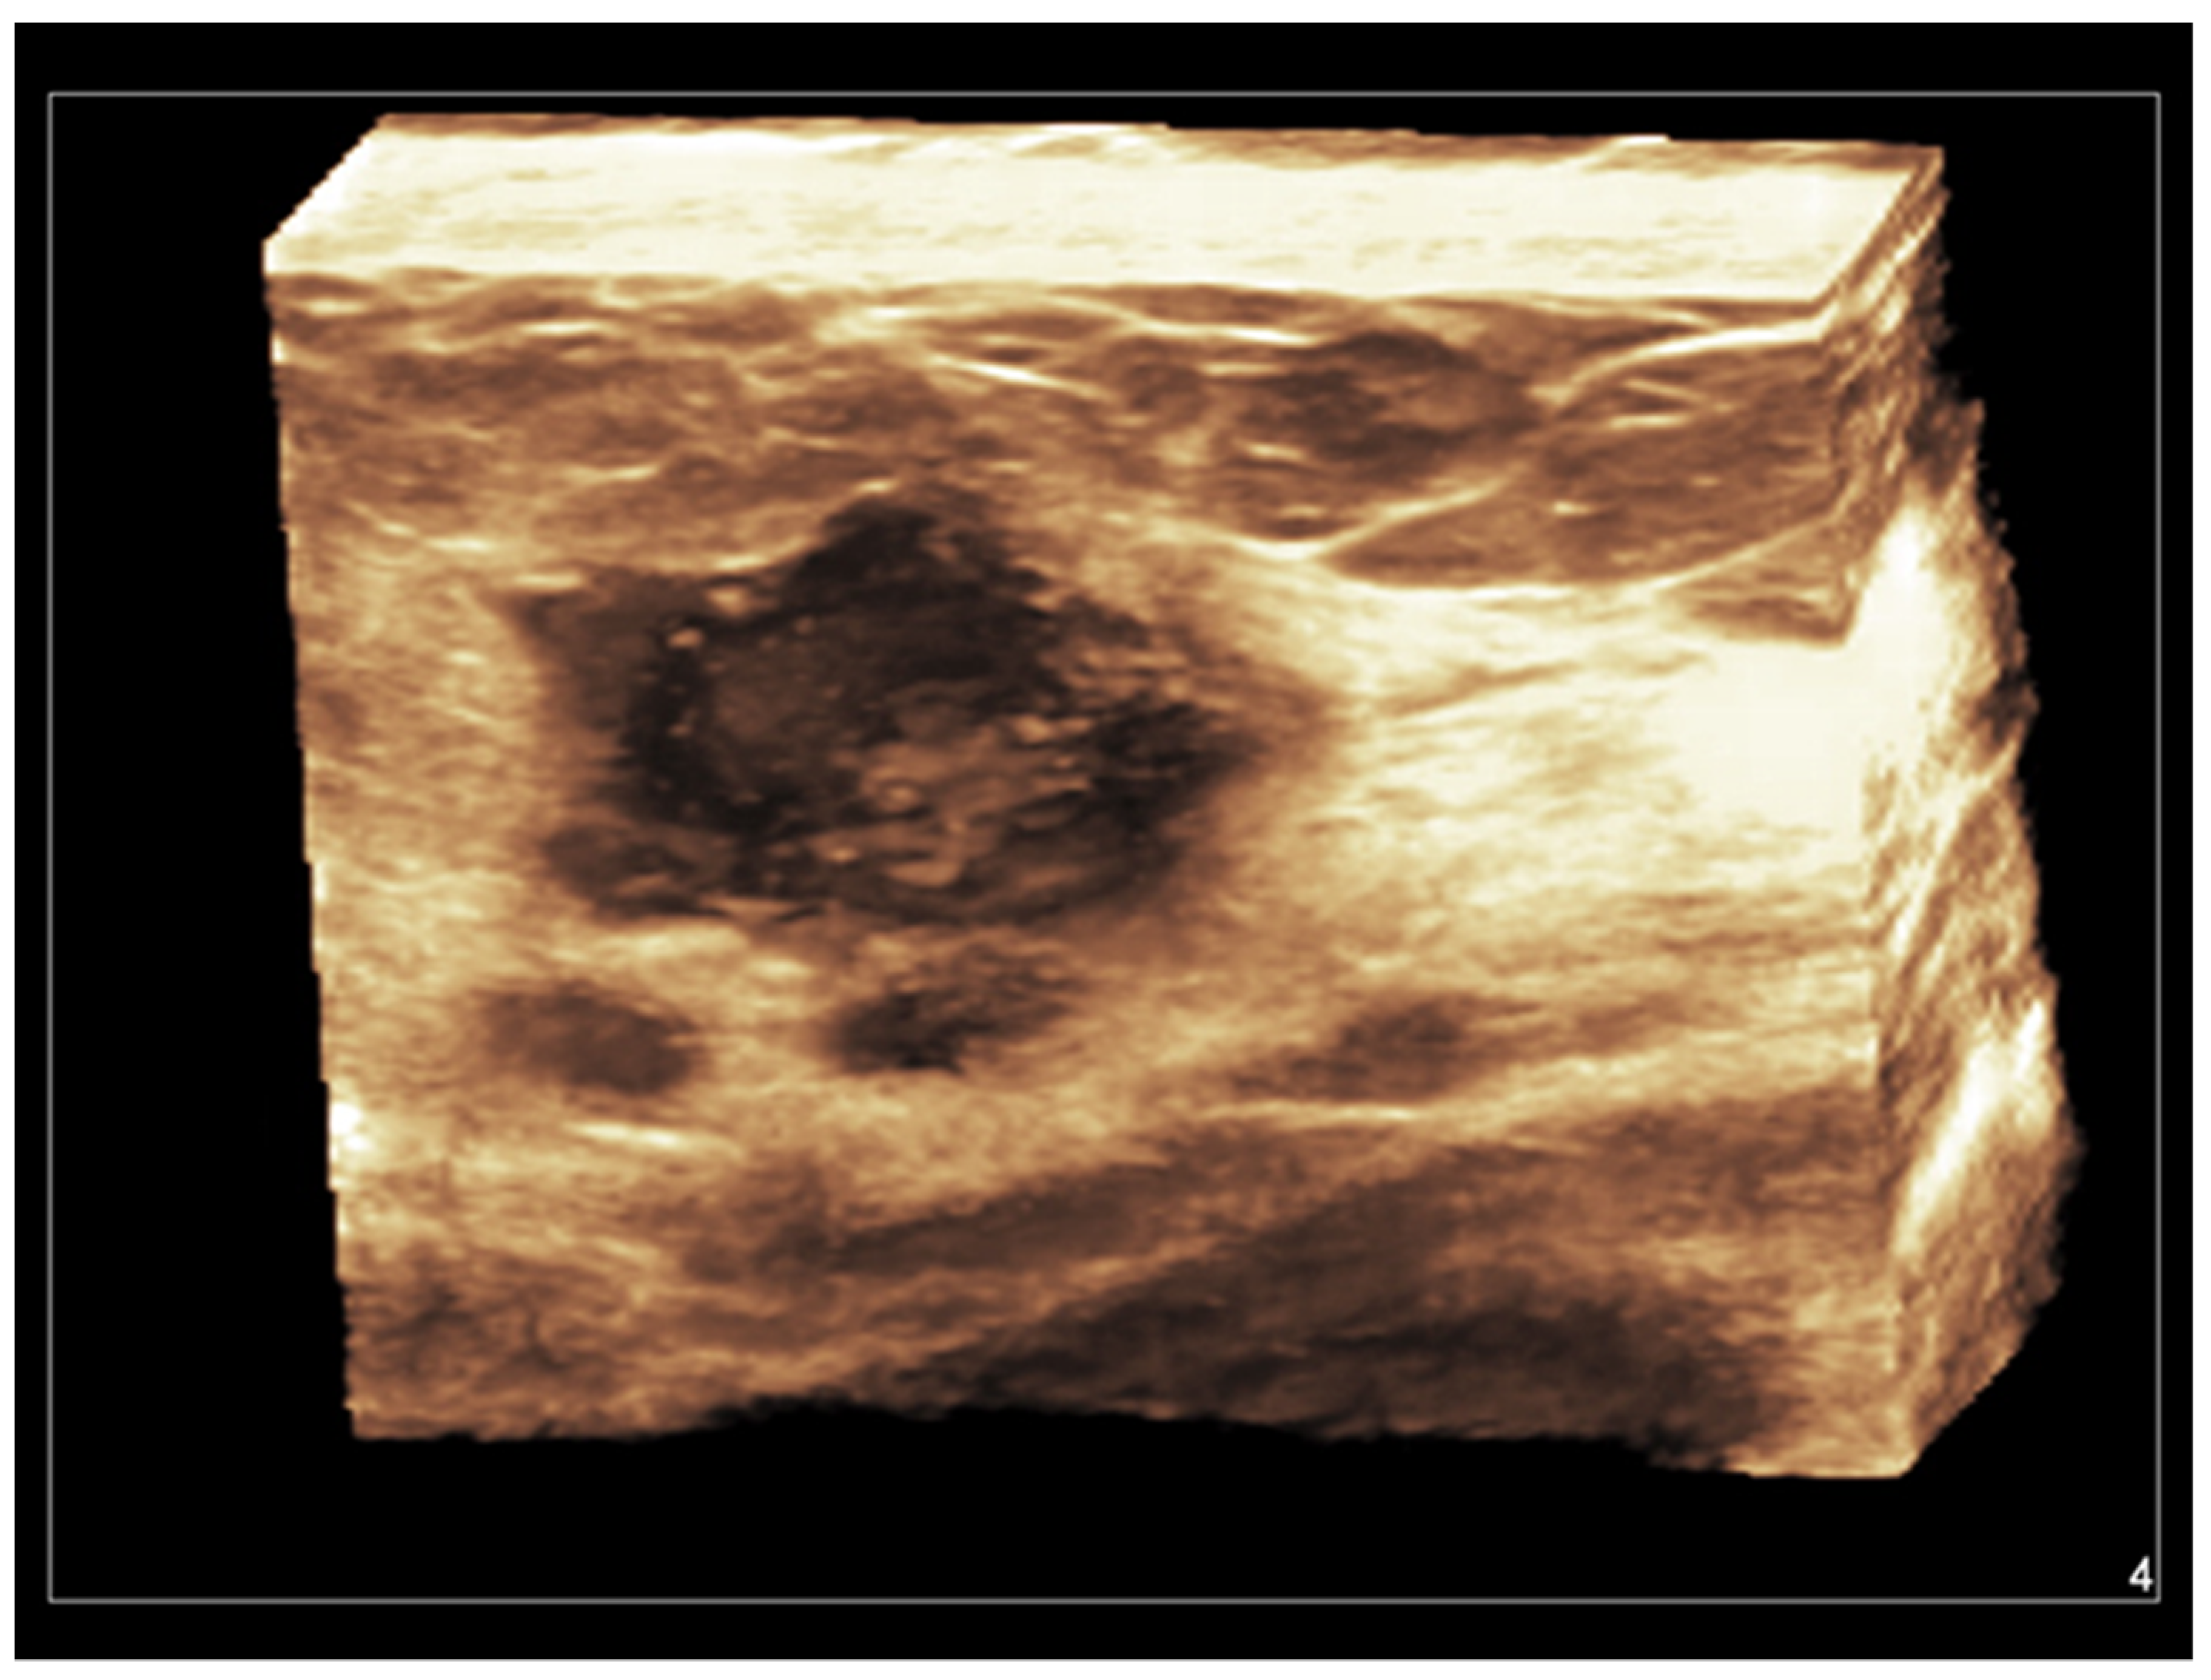

Figure 5. Invasive ductal carcinoma of the breast. Coronal 3D display of infiltrating tumor margins.

Both hand-held and automated linear transducers are available for use in high-resolution 3D breast imaging. Three-dimensional US, also called volumetric US, allows for obtaining a surface rendering of normal and abnormal breast structures. With a single pass of the ultrasound beam, a 3D reconstructed image is formed in the coronal, sagittal, and transverse planes, allowing a more accurate assessment of anatomical structures and tumor margins [11]. Coronal images, being parallel to the skin, represent a unique opportunity allowed from 3D US. A vivid representation of breast tumors can be obtained, with a retraction, star-like profile strongly supporting the diagnosis of malignancy [70,71,72,73,74] (Figure 5).